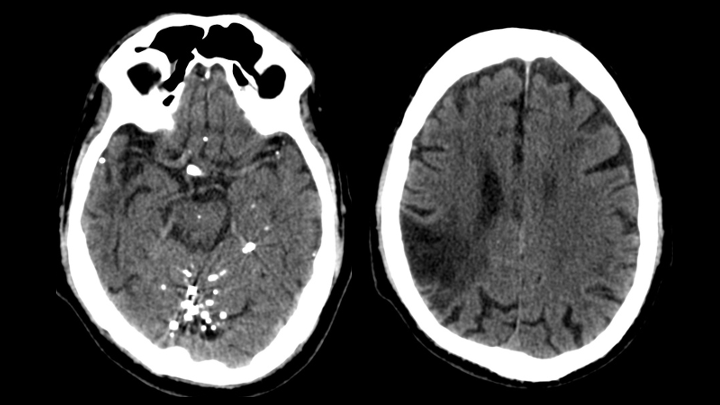

Se observan múltiples pequeños focos de material hiperatenuante dispersos en los espacios de circulación del LCR en la base del cráneo (localización extraaxial).

Se identifican múltiples pequeñas hiperdensidades intratecales, de tamaños variables.

El material presenta densidad metálica y genera artefactos en estría (streak artifacts).

El parénquima cerebral muestra cambios encefalomalácicos crónicos en territorio de la arteria cerebral media derecha, compatibles con secuela de infarto previo.

CONTRASTE OLEOSO INTRATECAL ANTIGUO (diagnóstico más probable)

También conocido como Myodil, fue un medio de contraste a base de aceite (nombre genérico: iofendilato) que anteriormente se utilizaba para la mielografía.

Desde 1944, Pantopaque fue aparentemente el agente intratecal más popular, ya que permitía una buena reproducción de la imagen con adecuado contraste entre los diferentes elementos intratecales; sin embargo, pronto se descubrió que causaba aracnoiditis, aunque se mantuvo en uso clínico hasta 1986, cuando la Food and Drug Administration finalmente prohibió su comercialización en Estados Unidos debido a su lenta eliminación (1 mL/año) y su alta osmolaridad.